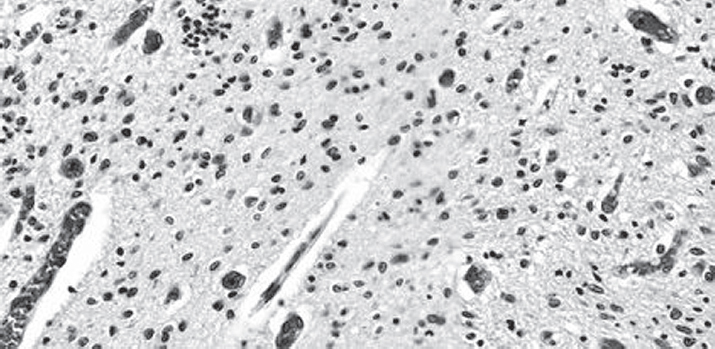

This article focuses on the problem of intraventricular hemorrhage in preterm infants with low and extremely low body weight. Premature newborns are most susceptible to this pathology due to the morpho-functional immaturity of brain tissues and blood vessels. Pathological factors lead to lesion of the vessel wall and a massive hemorrhage in the cavity of the ventricles, sometimes with a breakthrough into the white matter. The morphological findings of hemorrhage in the lateral ventricles of the brain in a child born with extremely low body weight are presented on an example of a clinical case. The article presents a description of the morphology of damage to the germinal matrix and choroid plexus as one of the most common sources of hemorrhage. The main attention is paid to the state of the blood vessels: arterioles, venules, capillaries. Possible causes and consequences of vascular injury in the periventricular region are indicated here. According to the recent studies, intraventricular hemorrhage appears more often due to damage to the choroid plexus in children born at 37 weeks of gestation and later. In this report we consider the problem of hemorrhage from the reducing germinal matrix’s vessels into the subependymal region with spreading into the white matter and lateral ventricles.